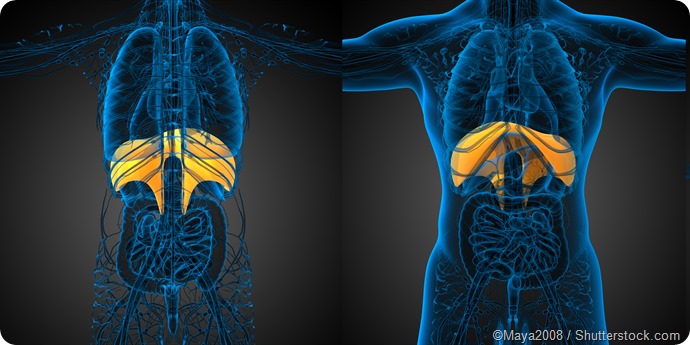

Hiccups occur as a result of the diaphragm suddenly involuntarily contracting. The diaphragm is the layer of muscle that separates the chest and abdominal cavities and plays an important role in controlling breathing. Tightening of the diaphragm causes the vocal cords to suddenly close, which results in the characteristic “hic” sound.

Illustration of diaphragm (yellow) in the body.